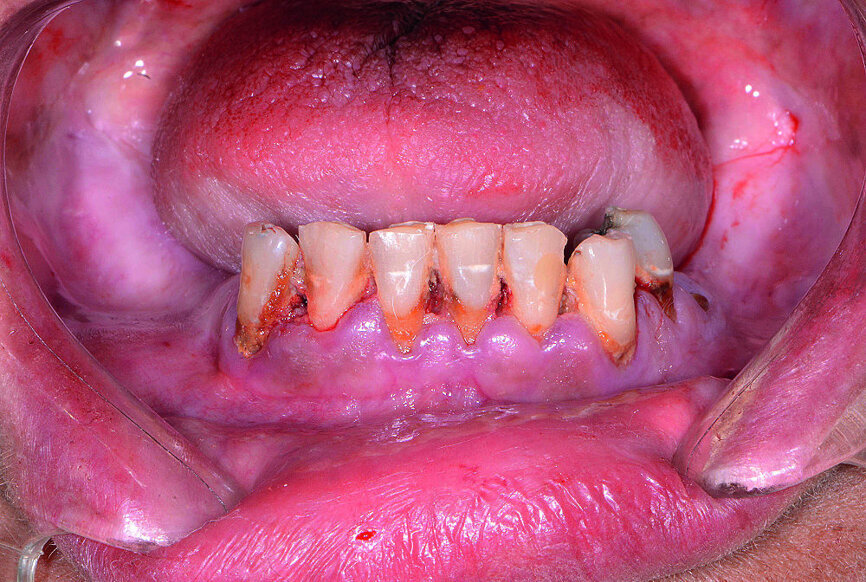

Ensuite, les dents mandibulaires, qui étaient irrécupérables (Fig. 13), ont été extraites à l’aide du davier Physics Forceps (GoldenDent), un lambeau a été décollé et une alvéoloplastie réalisée. Un guide chirurgical à appui osseux a été mis en place pour vérifier l’emplacement et l’angulation des ostéotomies implantaires (Fig. 14). Étant donné que les implants coniques Hahn sont pourvus d’un filetage auto-taraudeur, les filets profonds et tranchants, pénètrent dans les parois des sites alvéolaires et permettent de maintenir l’implant dans la position appropriée, par rapport à la paroi linguale. À la suite du nivellement osseux, on pouvait s’attendre à un gonflement des tissus, et des piliers de cicatrisation de 5 mm de hauteur ont donc été connectés aux implants de l’arcade mandibulaire (Fig. 15). Les prothèses immédiates ont été rebasées avec un matériau souple (Mucopren, de Kettenbach) afin de les insérer sur les piliers de cicatrisation, dont la forme en sablier et les zones rétentives assurent un degré de rétention qui améliore la fonction dentaire pendant la cicatrisation (Fig. 16).

Fig 13 Arcade mandibulaire anesthésiée

L’arcade maxillaire nécessitait une prothèse FP-3 en raison du degré élevé de résorption osseuse et de récession gingivale. Dans la mandibule, les contours tissulaires devaient également être recréés, ce qui exigeait un nivellement osseux, pour éliminer les contre-dépouilles, préparer une table occlusale idéale, placer correctement un guide chirurgical à appui osseux et établir une largeur d’os adéquate, qui permettrait la mise en place des implants.